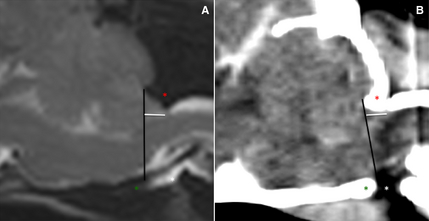

The two images above are (A) an MRI midsagittal T2WSE image and (B) a postcontrast CT image (soft tissue window) of the brain of the same CKCS. The supraoccipital bone (red asterisk), basioccipital bone (green asterisk) and occipitoatlantoaxial joint is visible (white asterisk). The foramen magnum limit is set (black line) from the rostrodorsal aspect of the supraoccipital bone to the most caudal aspect of the basioccipital bone. The cerebellar herniation length (mm, white line) is measured caudal from the foramen magnum. See also, this March 2014 item below.